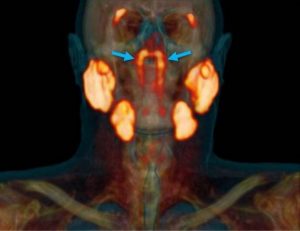

Un grupo de científicos de Países Bajos, han descubierto un par de glándulas que están escondidas en el cráneo humano donde se encuentra la cavidad nasal y la garganta. Esto durante una exploración diseñada para buscar crecimientos tumorales.

Esta “identidad desconocida” solo se logró captar cuando los doctores utilizaron un tipo de exploración nuevo llamado PSMA PET/CT que se ha aplicado para detectar la propagación del cáncer de próstata.

“Hasta donde sabíamos, las únicas glándulas salivales o mucosas en la nasofaringe son microscópicamente pequeñas (…). Así que imagina nuestra sorpresa cuando encontramos estas”, dijo Wouter Vogel, oncólogo radioterapeuta del Instituto del Cáncer de los Países Bajos.

Las “glándulas tubarias” recientemente descubiertas hicieron que se armara un debate en cuanto a si se trata de un nuevo órgano o si podían considerarse parte del sistema de órganos de las glándulas salivales.

Sin embargo, el estudio arrojó que “estos hallazgos apoyan la identificación de las “glándulas tubarias” como una nueva entidad anatómica y funcional”.